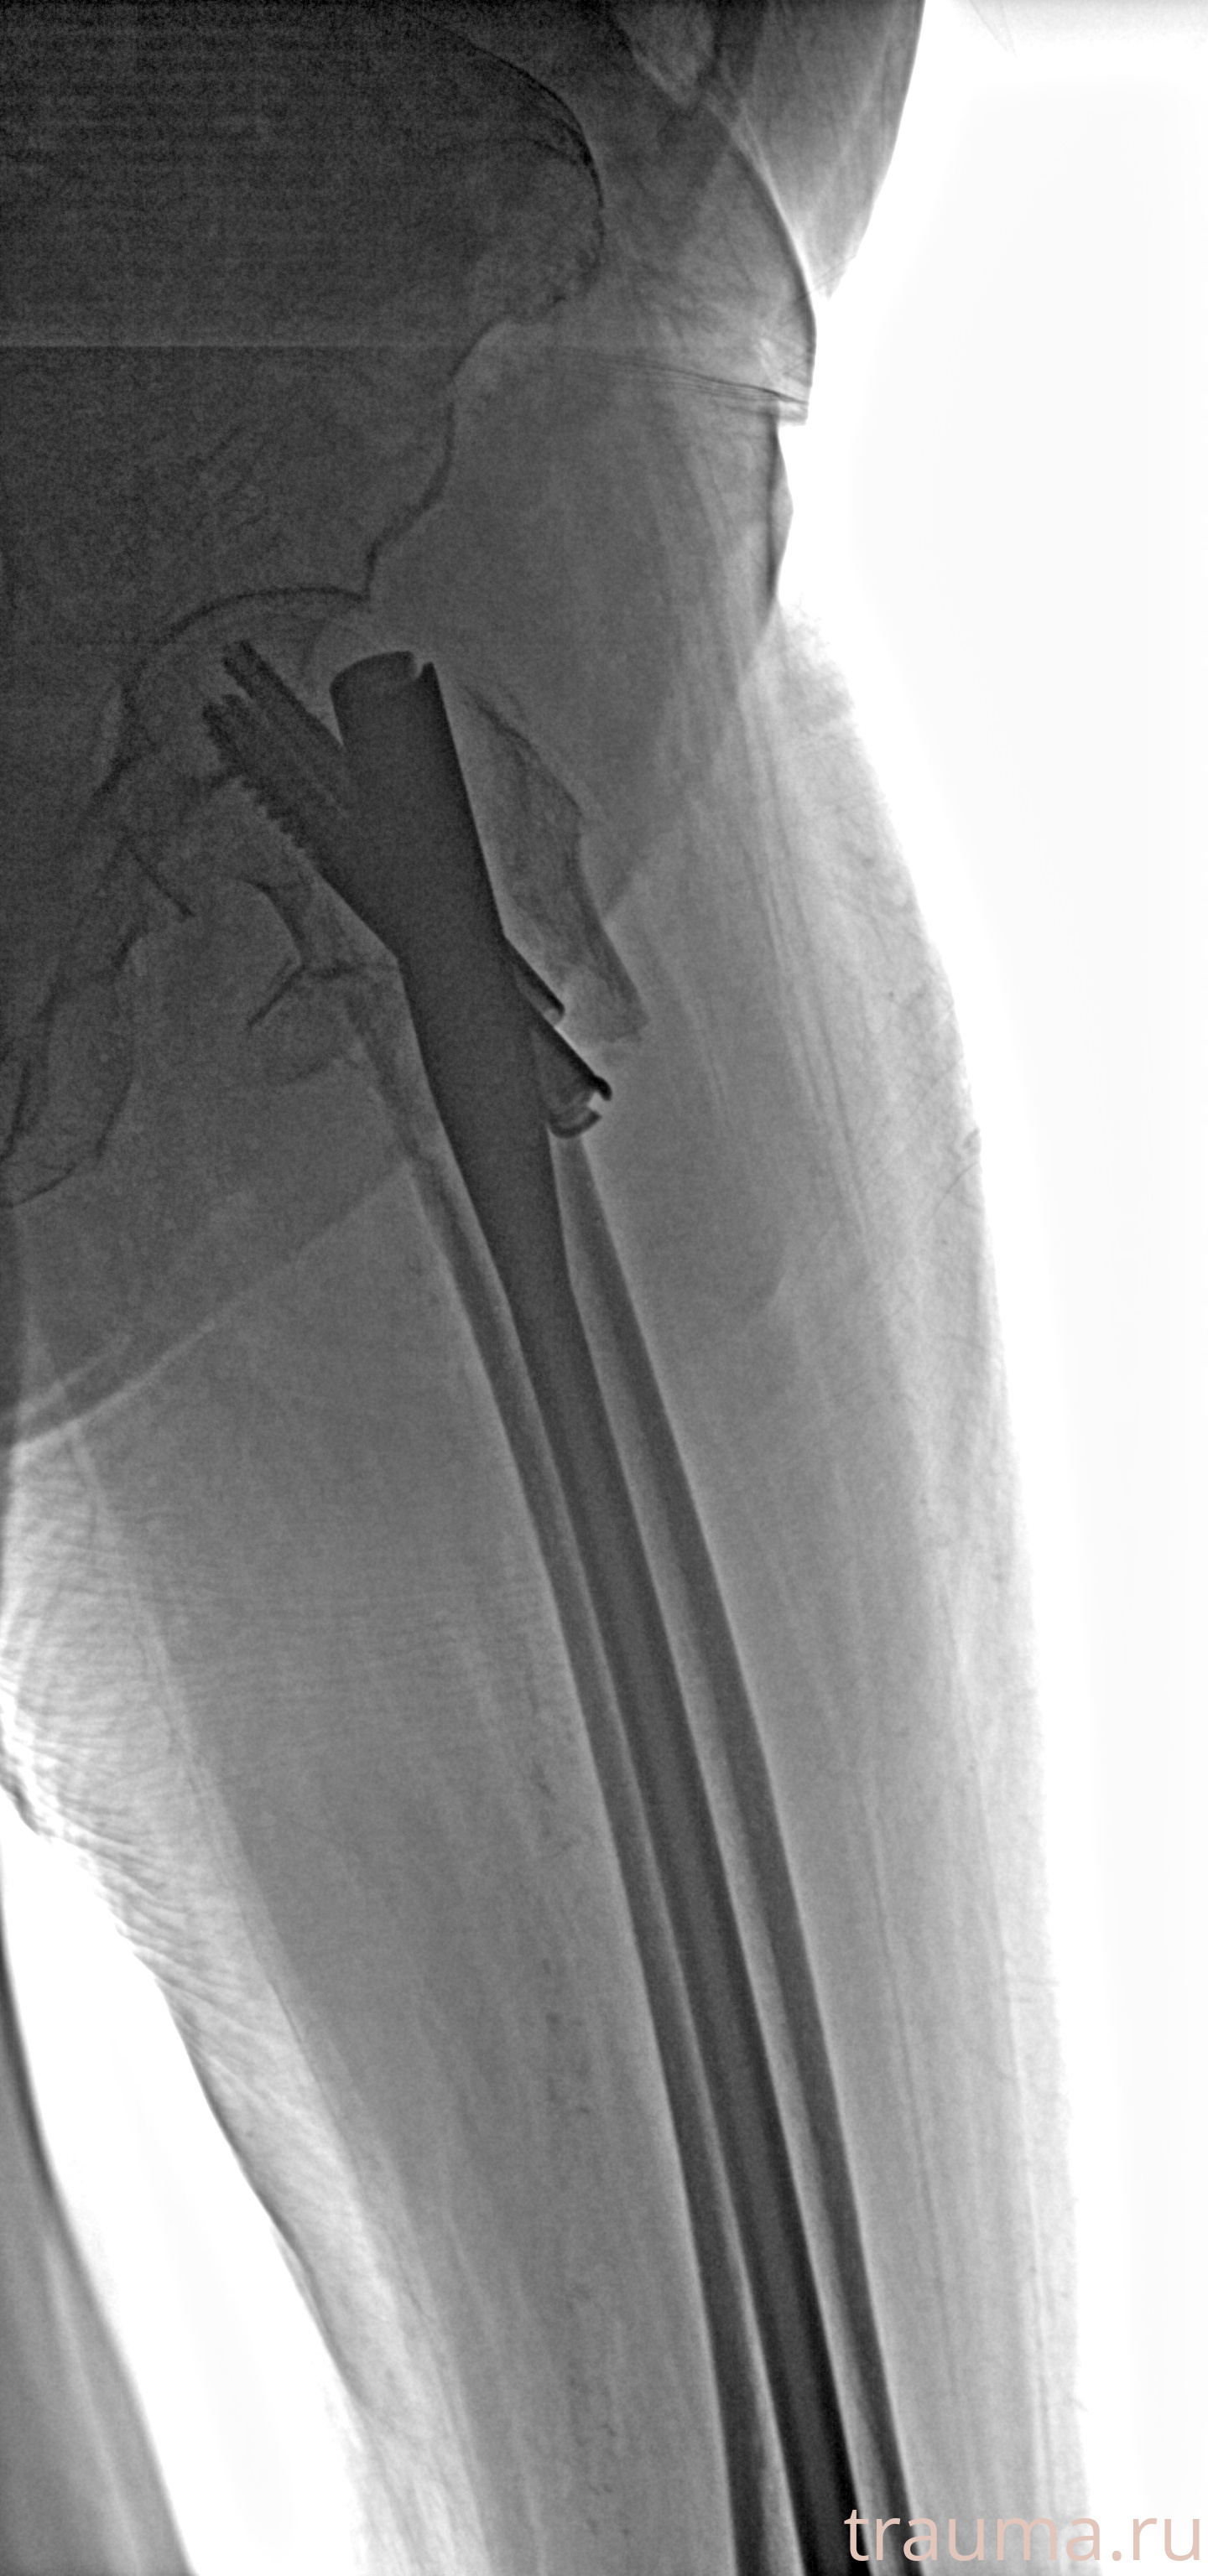

Рентгенограммы

Рентген на дому: по вашему адресу приезжает врач-рентгенолог, травматолог-ортопед с мобильным рентгеновским аппаратом, проводит диагностику травмы или заболевания, делает необходимые рентгенограммы, дает рекомендации по дальнейшему лечению. Получить качественные снимки в домашних условиях возможно благодаря уникальной методике, разработанной МосРентген Центром для института  Склифосовского